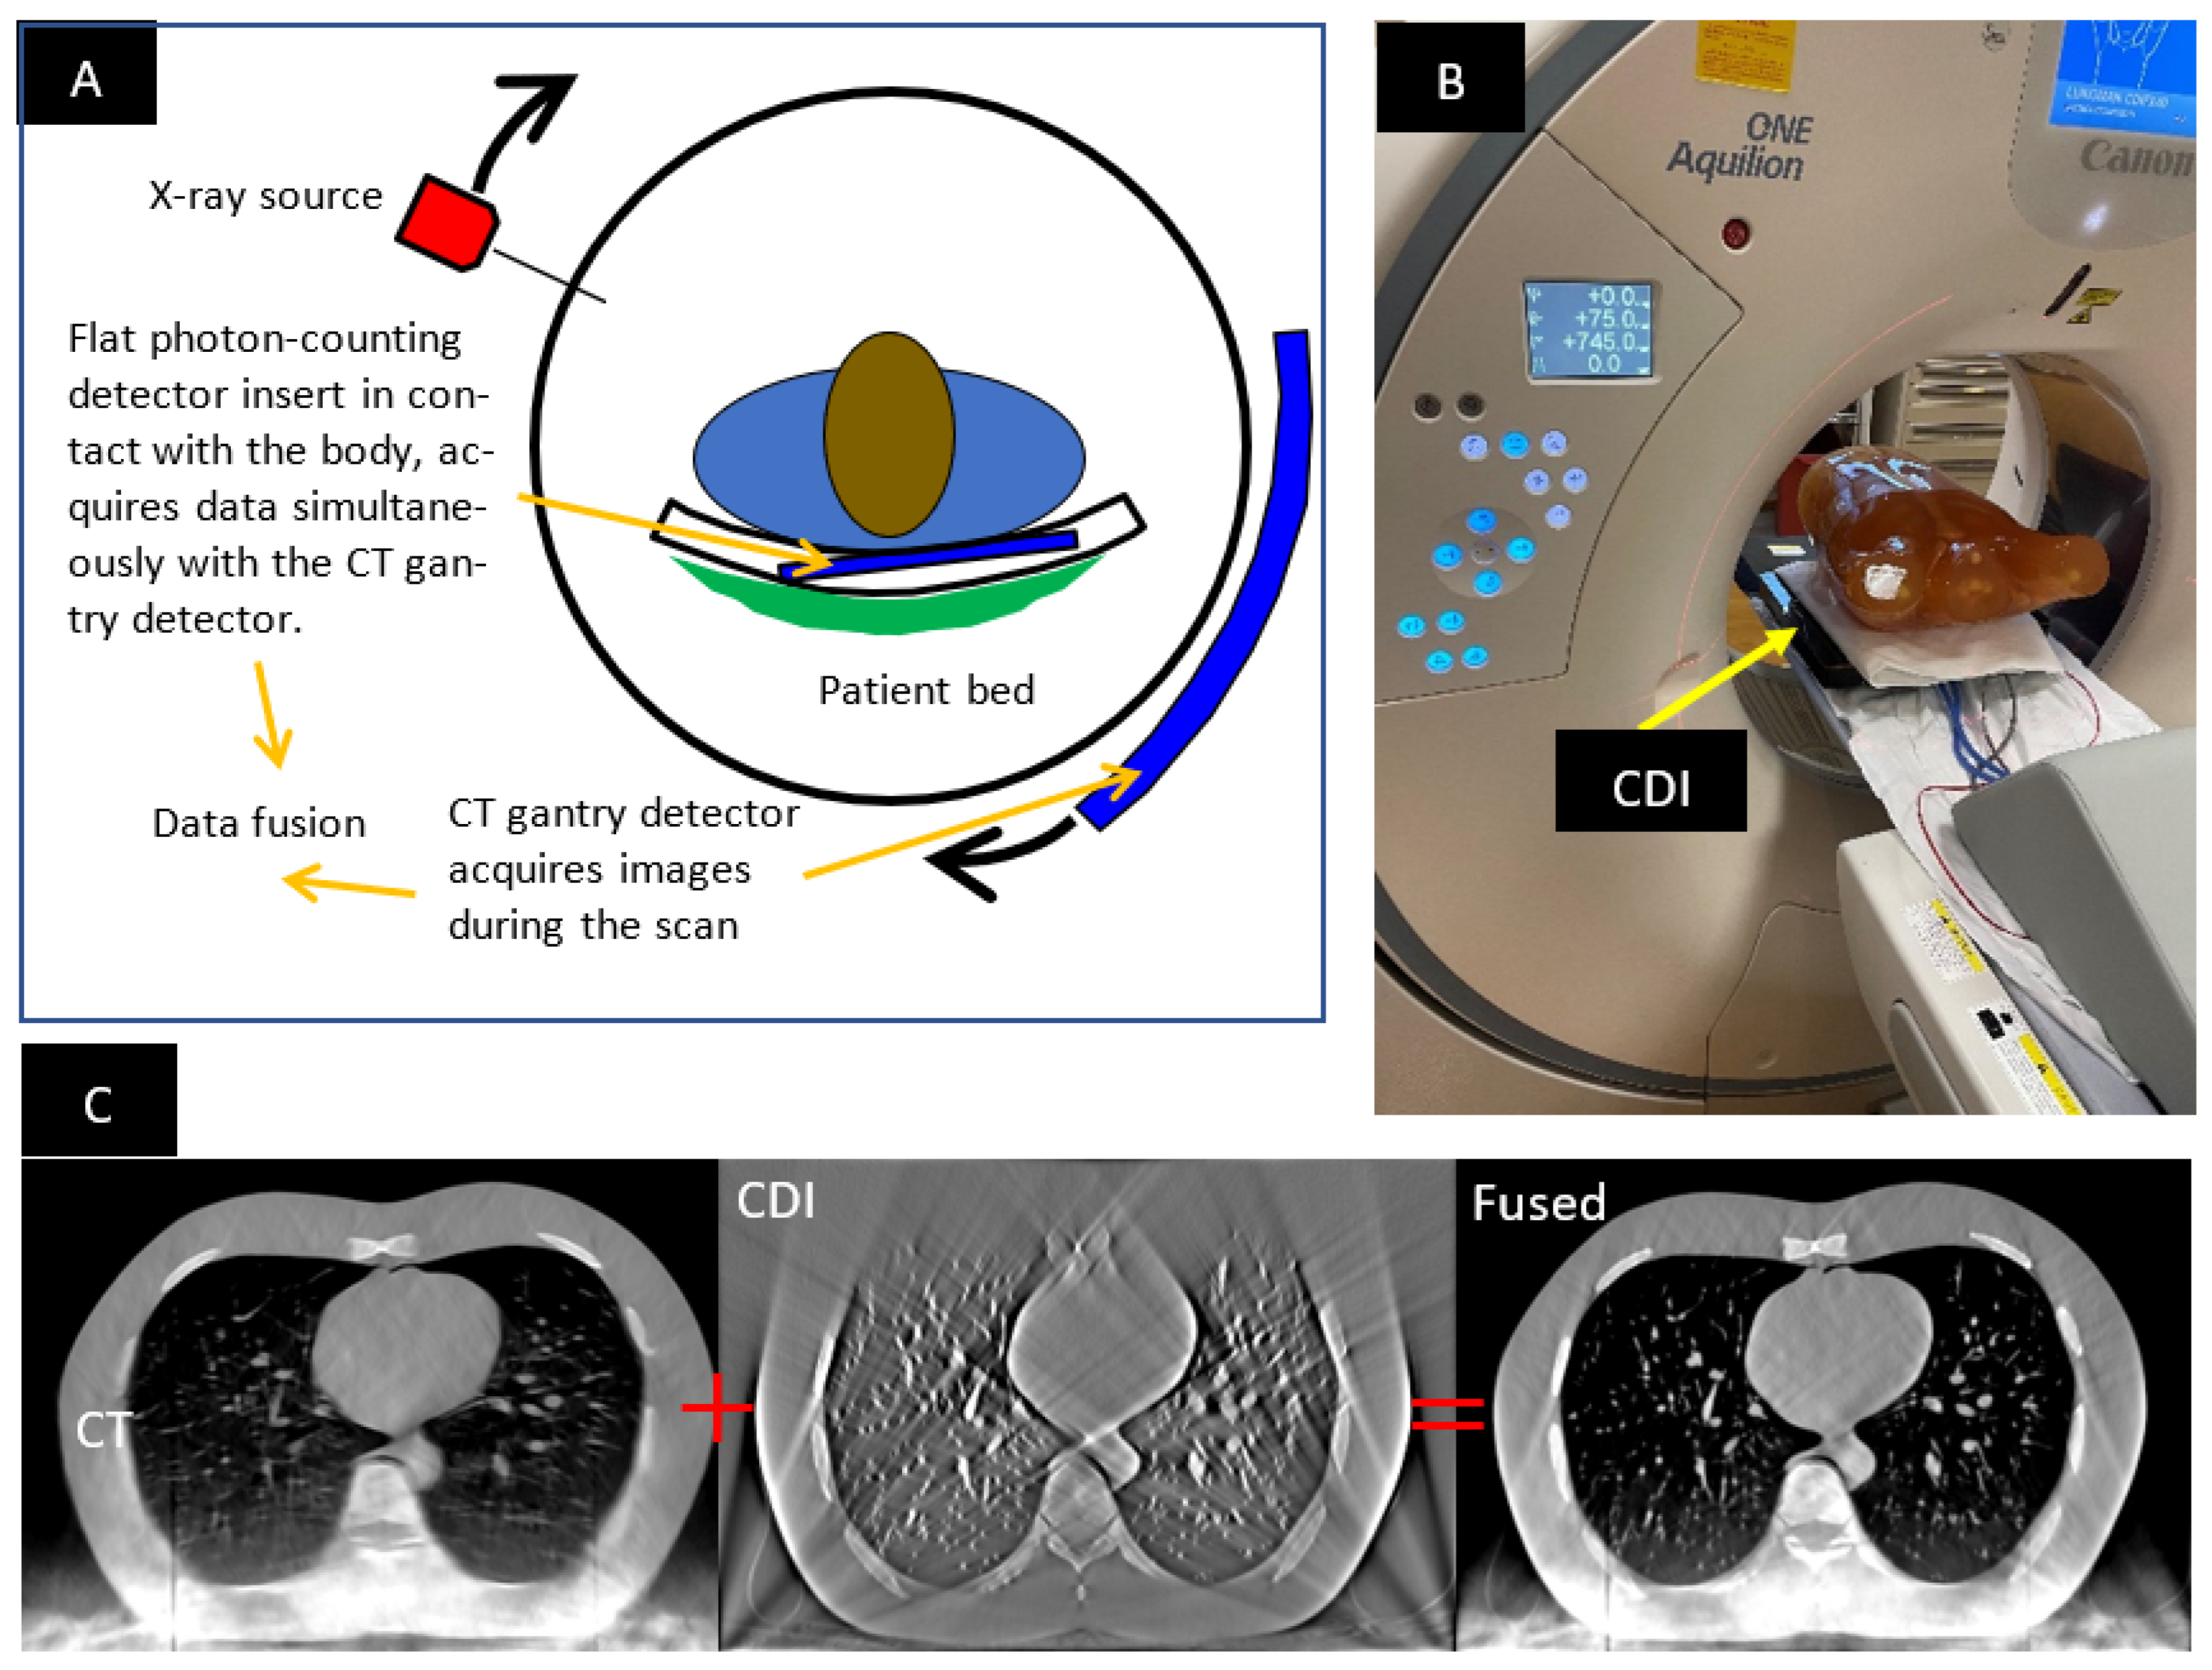

1.1. The Hybrid CT Scanner

2.1. Imaging Procedure and the Anthropomorphic Phantom